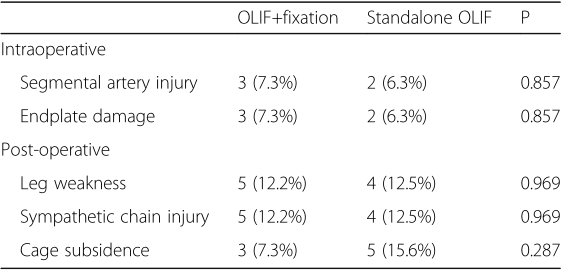

独立OLIF的总并发症发生率为25.0%,联合OLIF的总并发症发生率为26.8%。

OLIF联合治疗组分别在3个月和24个月时发生cage下陷,分别为7.3%(3/41)和7.3%(3/41),而6.3%(2/32)和15.6%(5 / 32)分别在独立的OLIF组中的相同时间点显示(P = 0.287)。两组在2年时均没有退笼。3个月时,联合OLIF组的融合率为85.4%(35/41),而独立OLIF组的融合率为84.4%(27/32)(P = 0.669)。在24个月时,联合OLIF组的融合率为100.0%,而独立OLIF组的融合率为93.8%(30/32)(P = 0.066)。